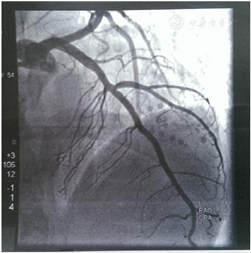

(1)外院心电图示:室性心动过速、ST-T改变(图1)。(2)外院动态心电图之一(1996年6月4日):平均心率77次/min,最快129次/min,最慢56次/min;见个别室早<64次;"RonT"、"插入性室早"、"室早成对"、"室性心动过速"等均系伪差干扰电脑误判,无ST-T改变(监护23 h)。(3)外院动态心电图之二(2019年8月6日):平均心率64次/min,最快94次/min,最慢52次/min;室性早搏936次,有1次成对室早,49阵室性二联律,无室性心动过速;房性早搏9个(4)上海交通大学医学院附属瑞金医院心电图(图2):QRS时限短,T波低平,I、avL肢导低电压。(5)胸X线:两肺纹理略多,未见确切活动性病变。(6)超声心动图(图3):心腔大小及厚度:左房内径33 mm,左室舒张末期内径52 mm,左室收缩末期内径41 mm,室间隔厚度6.5 mm,左室后壁厚度7.5 mm。二维:左室偏大,左室壁不增厚且心肌厚度不均匀,心尖处最薄,部分区域心肌组织较疏松。静息状态下左室壁各节段收缩活动减低,尤以心尖部最明显。各心瓣膜未见明显增厚,开放不受限。右室壁未见明显变薄。左心功能测定:左室舒张末期容量118 ml,左室收缩末期容量63 ml,左室射血分数46%,左室短轴缩短率23%,每搏输出量55 ml。结论:左室壁心肌厚度不均匀,心尖处较薄,部分区域心肌组织较疏松,综合考虑心肌病可能较大。(7)为进一步明确病因,完善冠状动脉造影,结果提示大致正常(图4)。(8)CMR:左室壁心肌厚度不均,左室前壁及心尖处较薄,增强后左室前壁心内膜下可见片状强化,未见反常运动和矛盾运动,左室射血分数41%。结论:左室壁心肌厚度不均匀,左室功能不全,提示非缺血性心肌病变(心肌致密化不全可能,图5)。